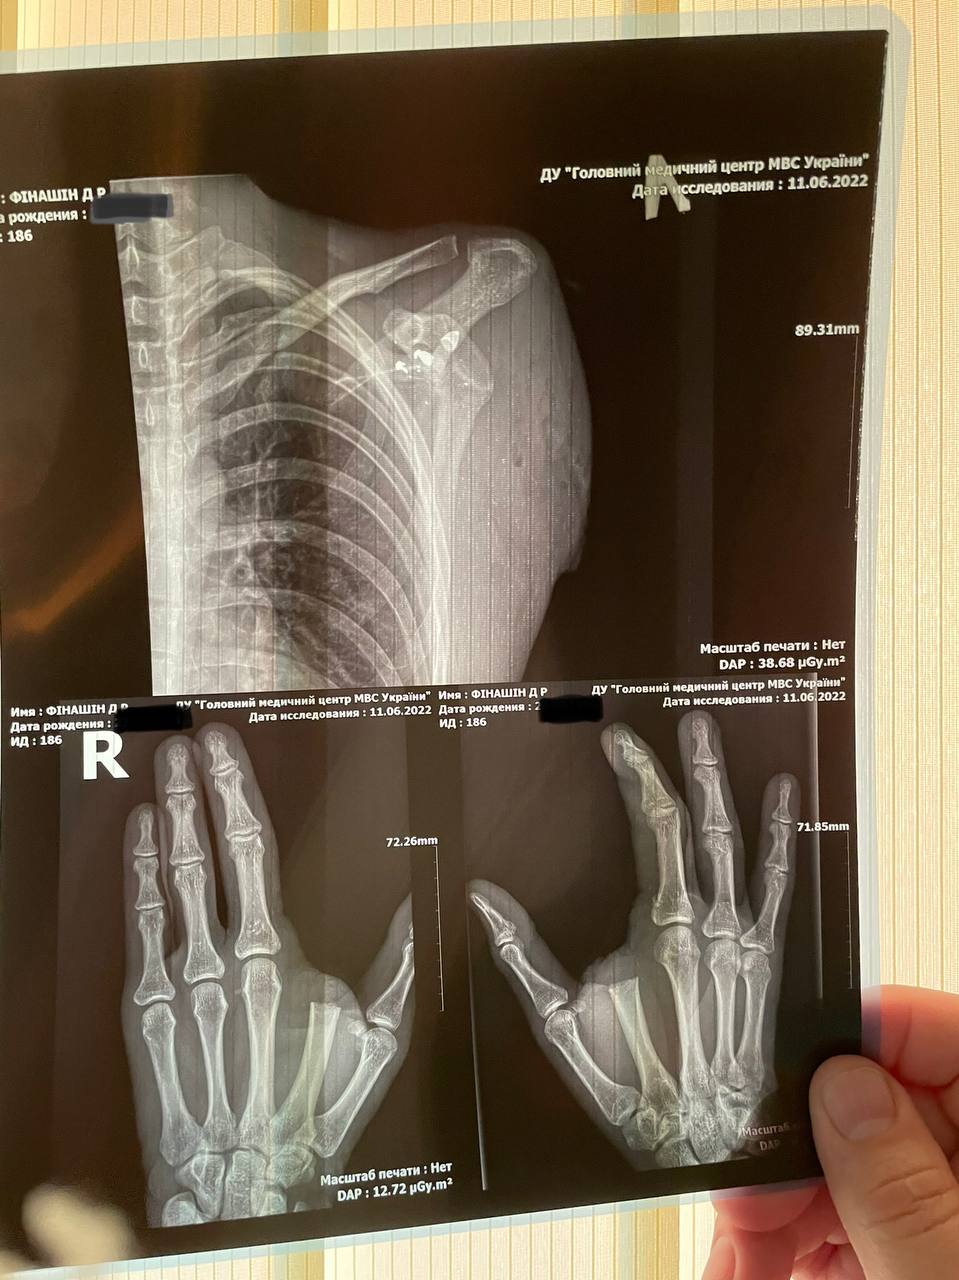

Один побратим загинув від російських куль одразу, ще одного поранили. Одна з куль «Фіну» відірвала вказівний палець правої руки, інші влучили в шолом та ліву руку. Але під час бою група знищила кілька одиниць техніки та піхоту противника і зуміла витіснити ворога з важливої висоти.

У польовому шпиталі «Фіну» ампутували руку та палець — врятувати їх було неможливо. Але про це Дмитро здогадувався і до цього — два дні з накладеним на кінцівку турнікетом не давали шансів.

Лікарі назвали не інакше як дивом той факт, що Фінашин залишився живим — він мав зневоднення, погано працювали нирки, організм був вражений сепсисом, на ампутованій кінцівці розвилася гангрена. Попри побоювання медиків, ввечері після чергового операційного втручання, перебуваючи ще в реанімації, чоловік вже їв. А менше ніж за місяць він був виписаний на реабілітацію додому. Така була жага до життя.